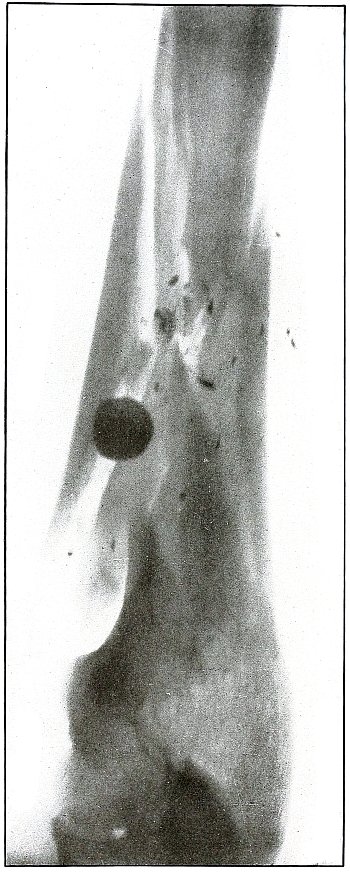

Rifle—Plate 53.

UPPER EXTREMITY.

Gunshot Fracture of the Shaft of the Femur

with Lodgment of the Bullet.

The course of the bullet was antero-posterior and diagonally inward

from the antero-external border of upper third of the thigh. A thin

longitudinal fragment was split off without transverse fracture.

The missile struck the thigh after its energy had been greatly

reduced by ricocheting as a result of striking a resisting object

which flattened its nose and “set up” its body, as shown by the wavy

outlines of the shadows.

The dense and normal-size shadow shows the bullet to be near the plate

and probably in the muscles superficially behind and below the lesser

trochanter.

As the prominent outline of the lesser trochanter shows that the

leg was in external rotation when the negative was made, it is

evident that, with the rotation back to the anatomical position, the

projection of the shadow of the bullet would fall close to or in line

with the shaft of the femur; the position of the bullet is behind the

femur.

The treatment is conservative, with no trouble to be expected from infection.